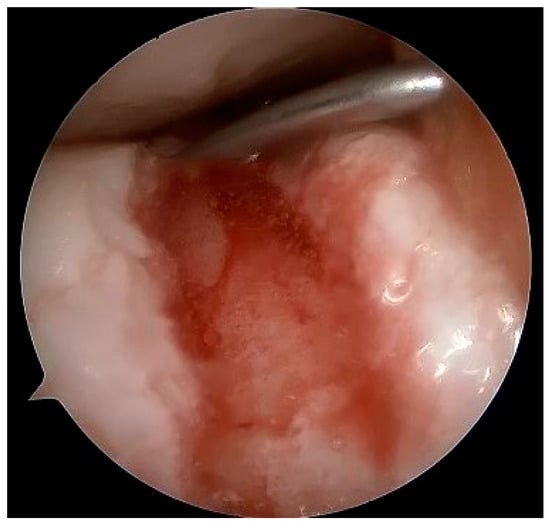

Figure 11.

Dry arthroscopy view of a full-thickness cartilage injury in the femoral trochlea after debridement and preparation for matrix implantation.

Figure 12.

Dry arthroscopy view of the same defect filled with cell-free matrix gel.